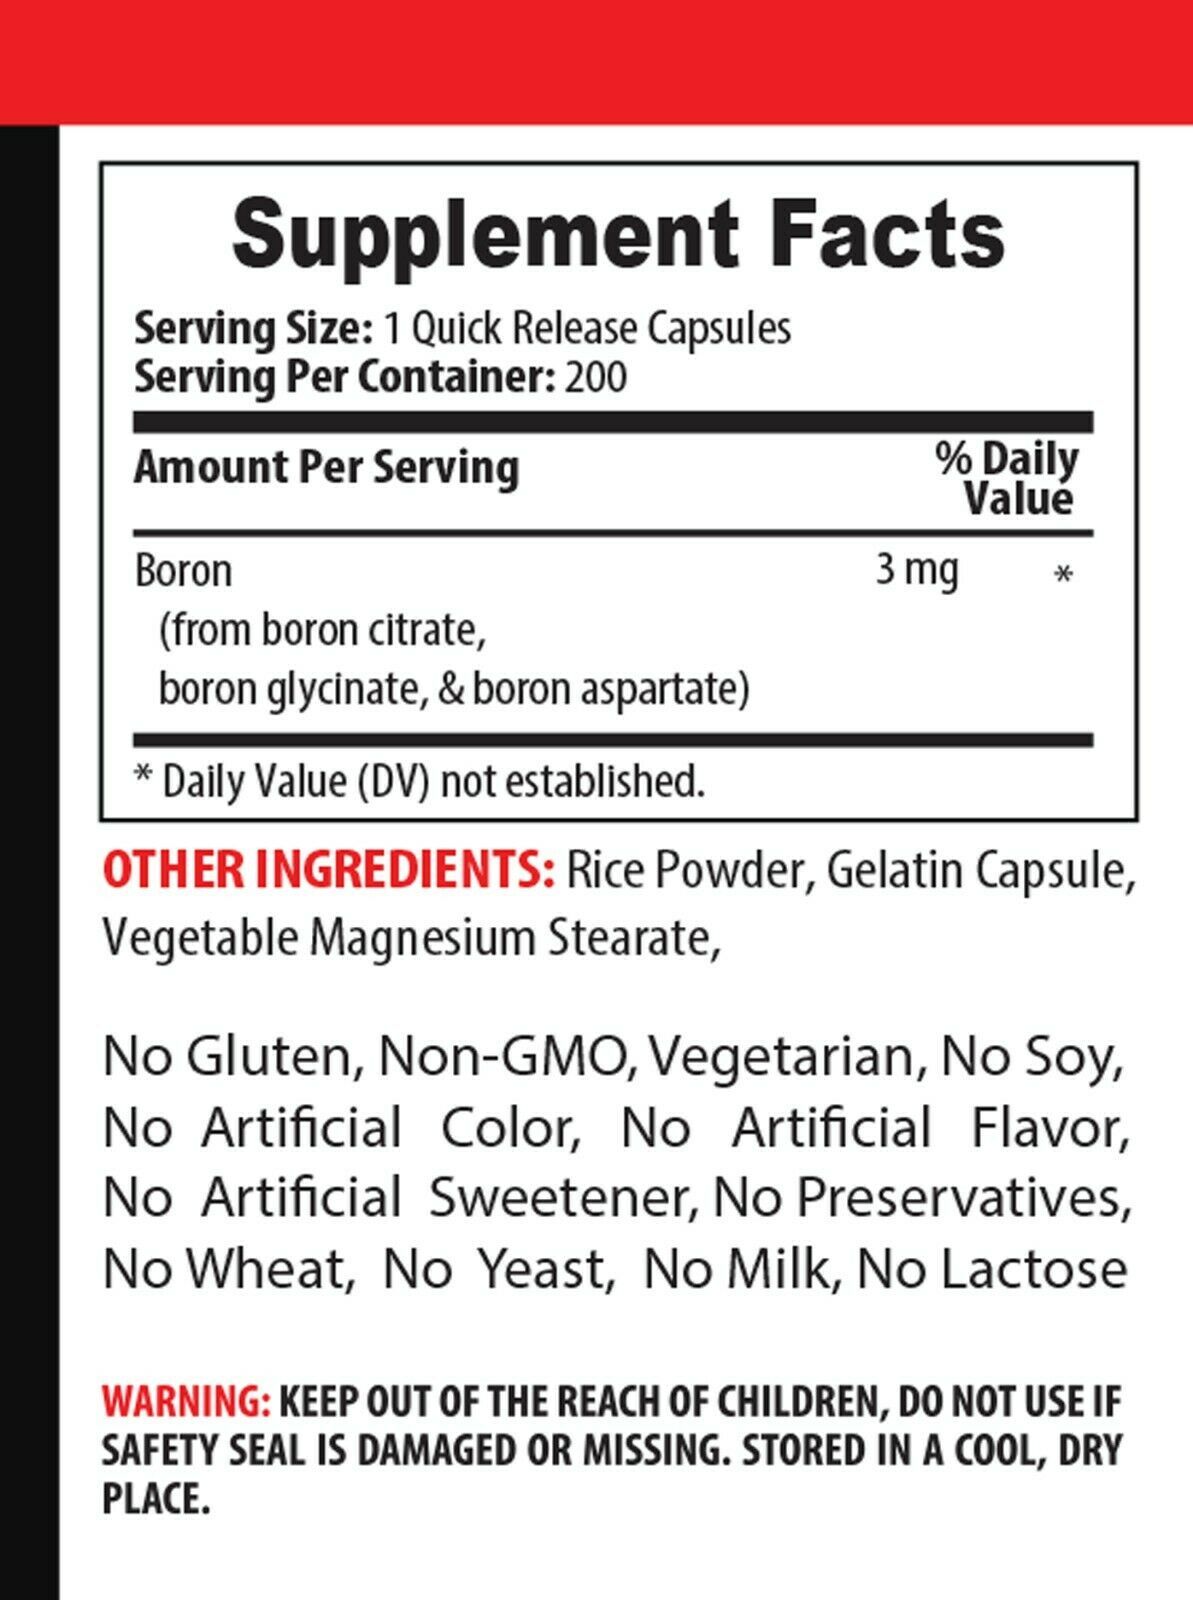

bone and joint vitamins for men - BORON COMPLEX - boron bone 2B

Item traits

| Category: | |

|---|---|

| Quantity Available: |

10 in stock |

| Condition: |

New |

| UPC: |

300873012026 |

| Brand: |

Evolv Supplements |

| Country/Region of Manufacture: |

United States |

| Expiration Date: |

05/2022 |

| Gender: |

Unisex |

| Formulation: |

Capsule |

| Active Ingredients: |

Boron |

| Main Purpose: |

Multi Purpose |

| Type: |

Multimineral |

| Features: |

All Natural |

| Ingredients: |

Boron |